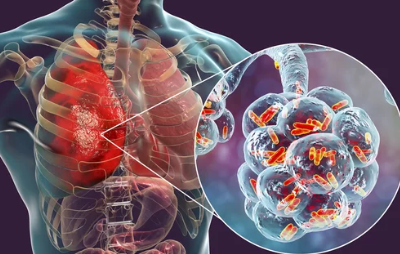

4. 점차 악화되는 폐 기능

방사선 폐렴이 치료 없이 방치되면 폐 기능이 점점 악화될 가능성이 높습니다.

- 폐활량 감소:

폐가 딱딱해지는 섬유화 현상이 진행되면서 숨을 깊이 들이쉬기가 어려워지고, 폐활량이 감소합니다. - 산소 부족 증상:

피부가 푸르스름해지는 청색증이 나타나거나, 운동 중 어지러움이나 혼란 상태가 발생할 수 있습니다. - 만성 폐질환으로 진행 가능성:

초기 단계에서 치료하지 않으면 만성 폐섬유증으로 발전해 장기적인 호흡 문제가 생길 수 있습니다.